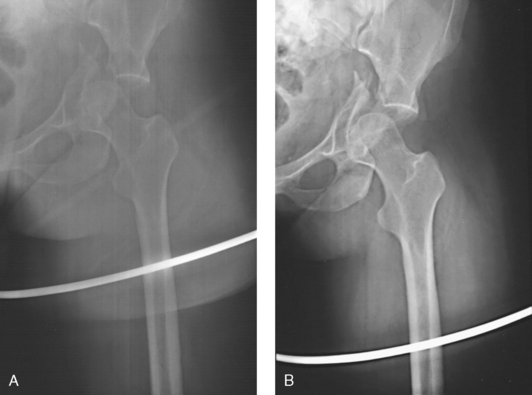

Fig. 28-11 Mobile AP chest radiographs in critically ill patients. A, Patient with postoperative left thoracotomy and chest tube, infiltrate or atelectasis in the left base, segmental elevation of the right hemidiaphragm, and soft tissue emphysema on the left. B, Patient with small left pleural effusion and moderate right effusion, cardiomegaly, mild pulmonary vascular congestion, and calcification and torsion of the aorta.